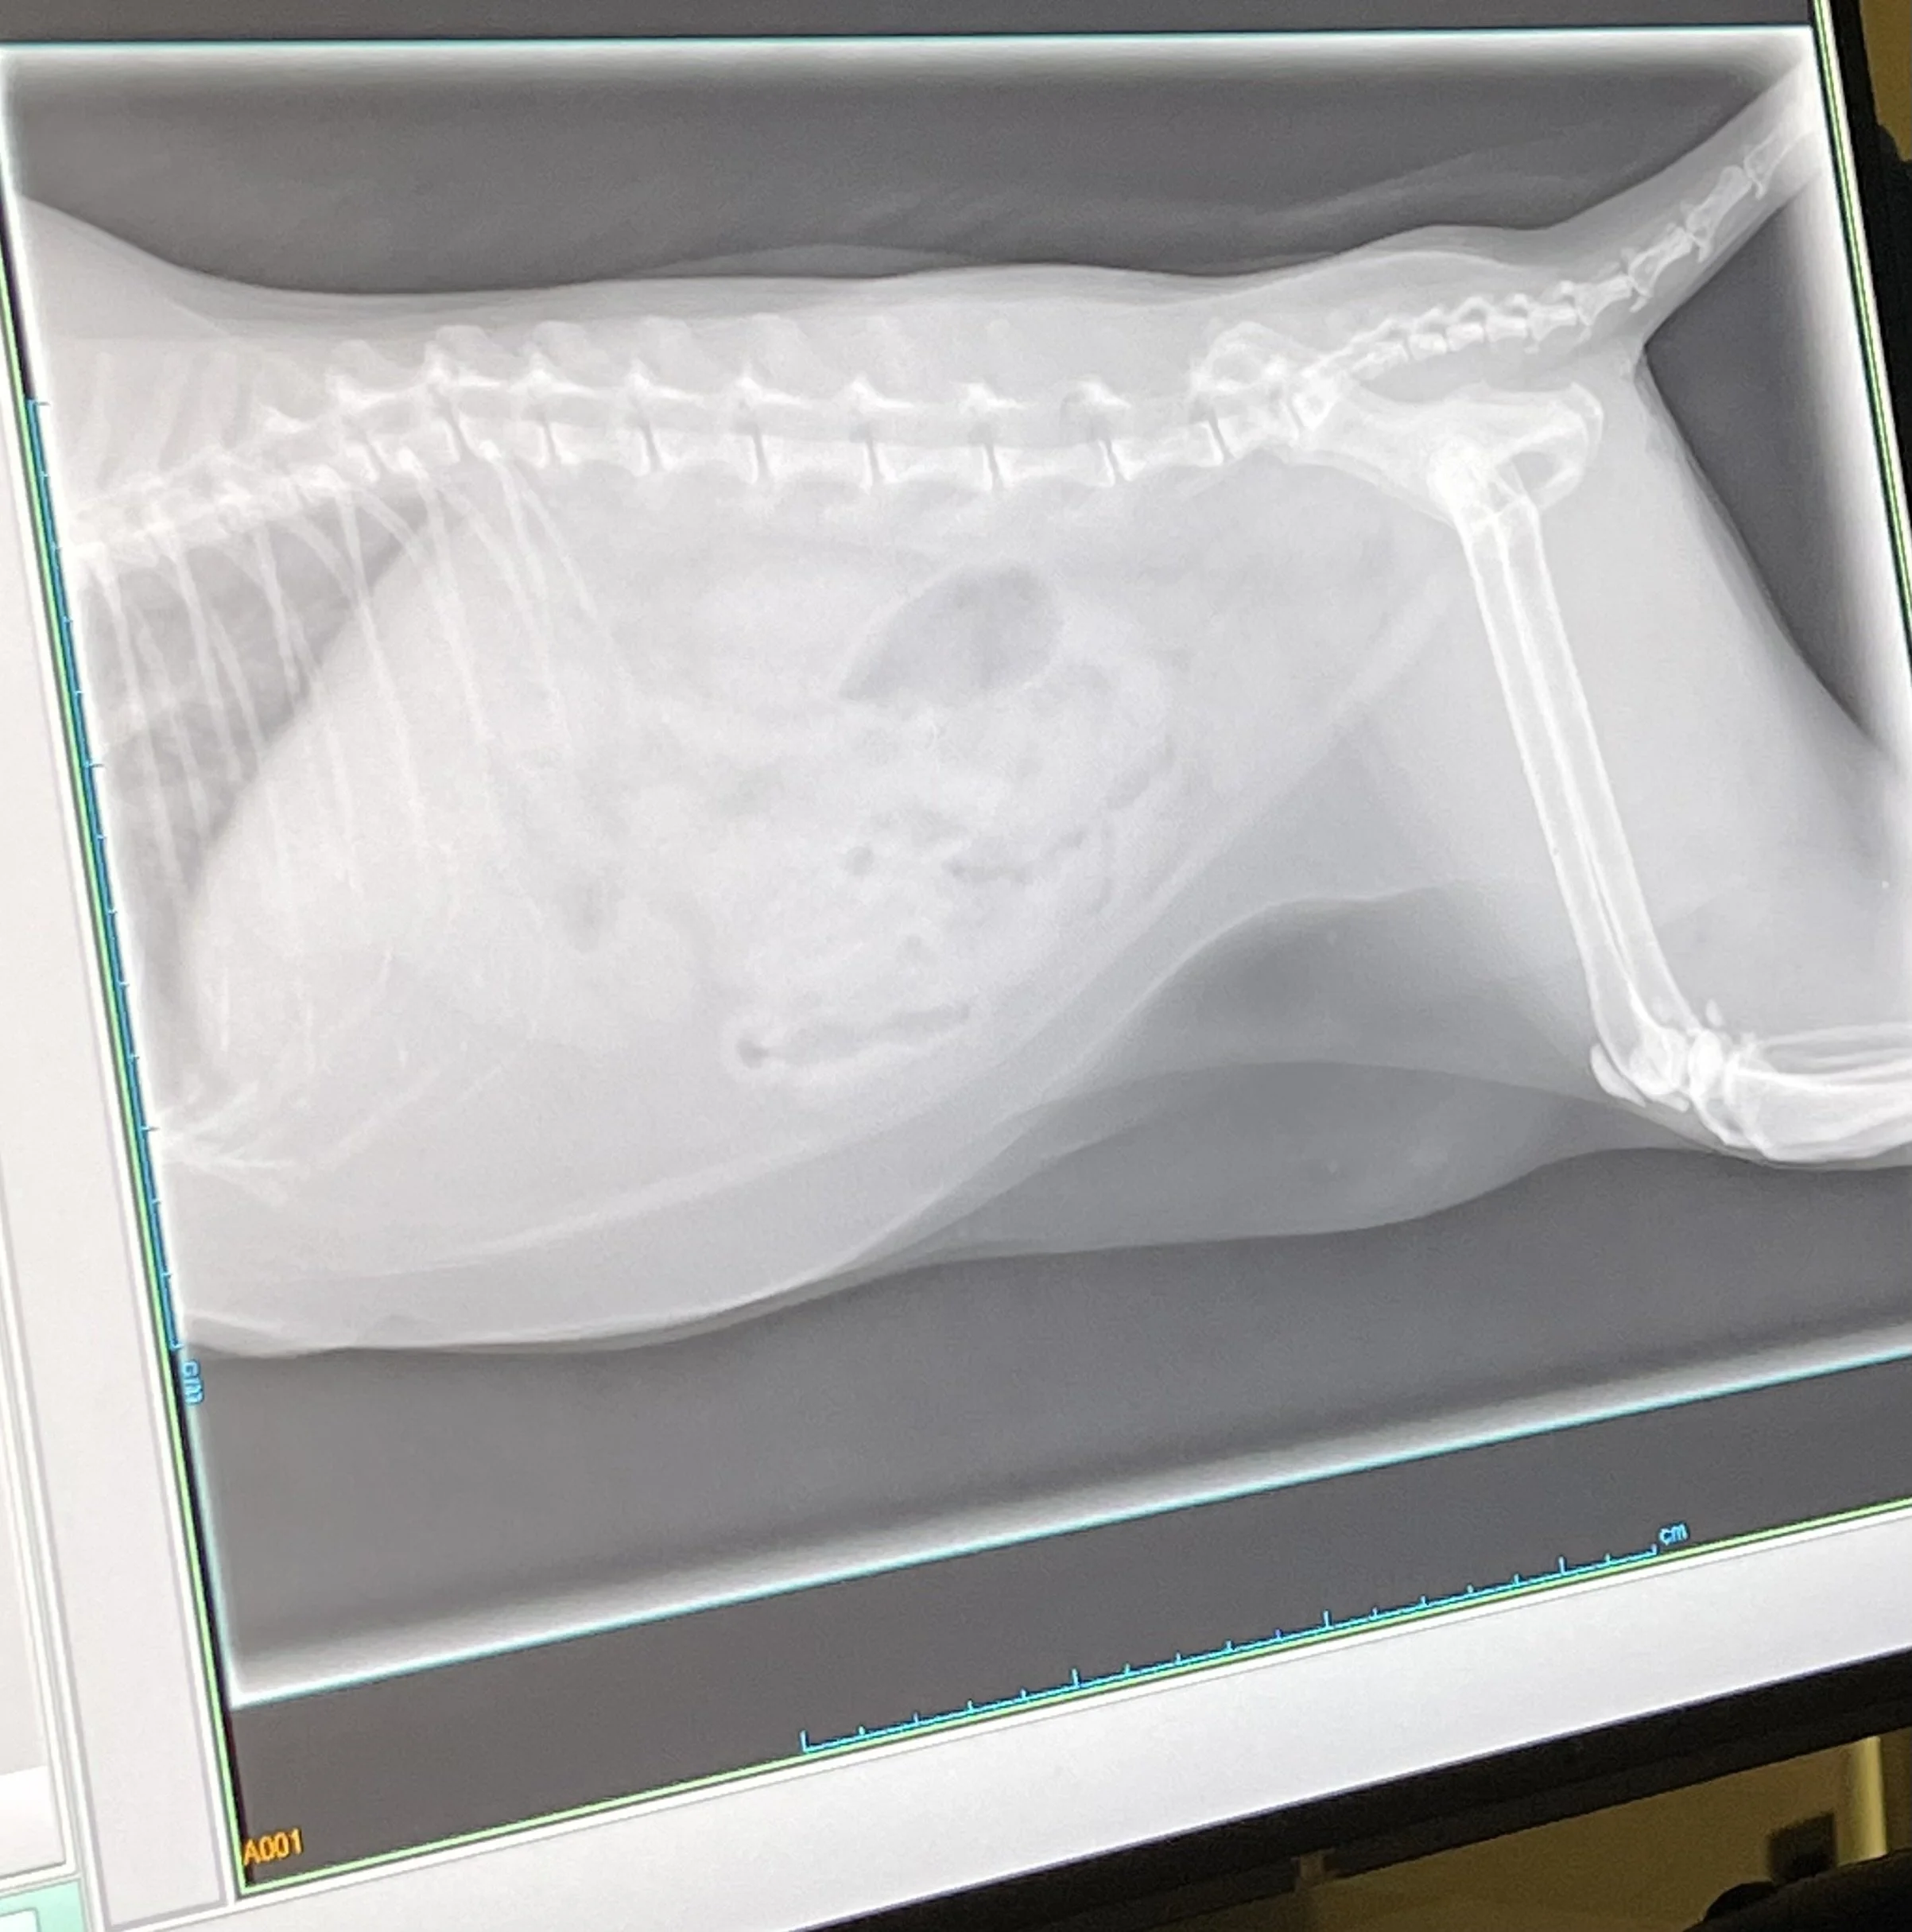

Next was the operation room. There was an X-ray machine. We were able to see a real X-ray photograph. It was a cat’s photograph. The vet showed us the heart, bones, and legs. Wow! It was very interesting! “Arigatou!” When we were going to leave, she gave us a special gift. It was a bag with stickers inside! “Can I take it home?” “I like the stickers!” We were very happy about the special present. Once again, we thanked her.